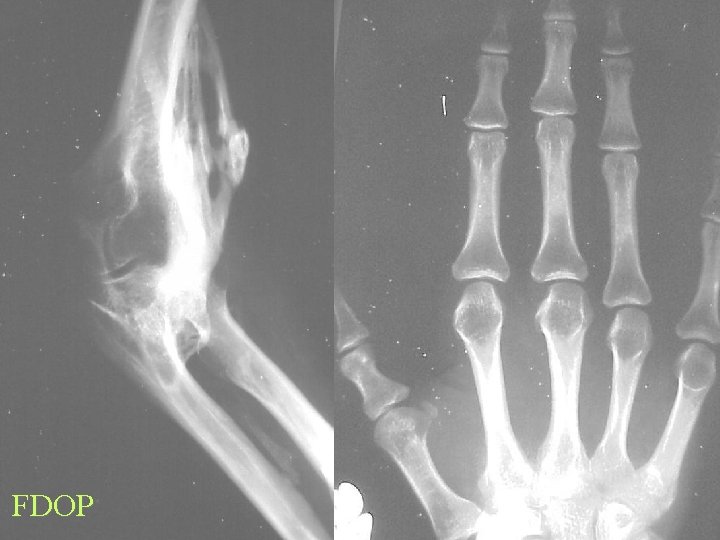

FDOP